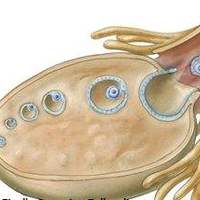

卵泡闭锁是指卵泡在发育过程中停止生长或萎缩的现象。达必佳能够遏制卵泡闭锁,保证卵泡的正常发育和成熟。通过注射达必佳,可以防止卵泡过早闭锁或异常发育,从而提高试管婴儿的成功率。